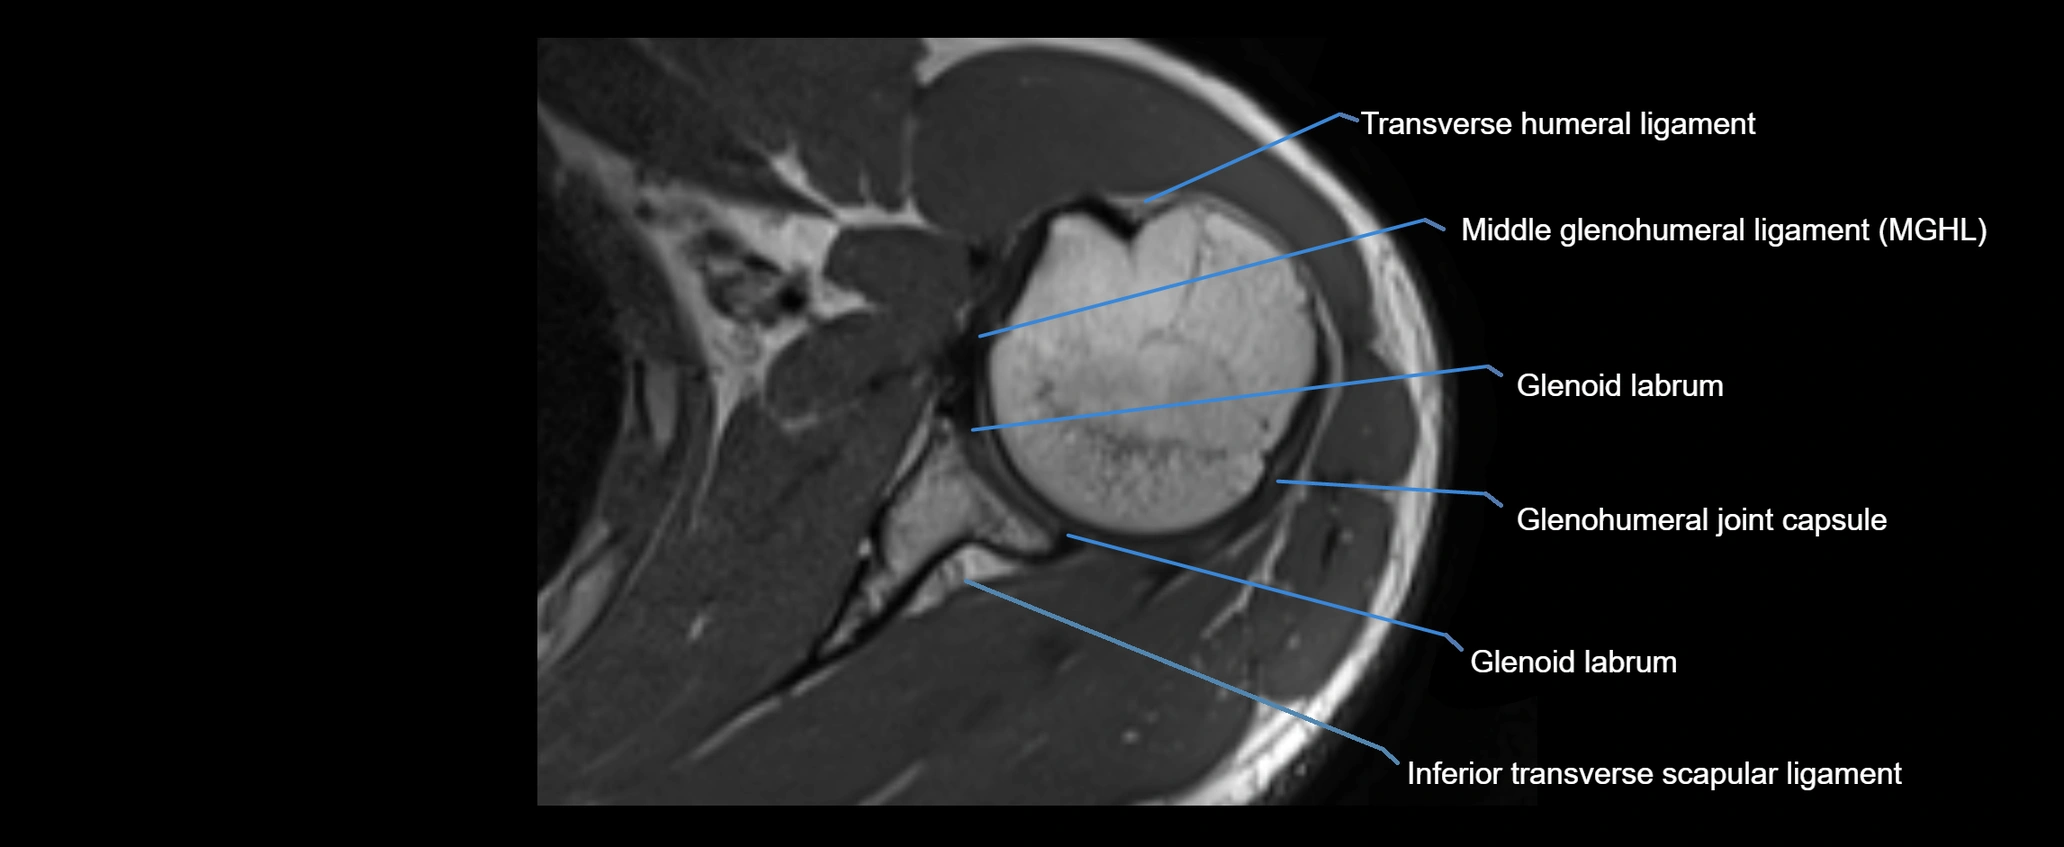

CT image

image